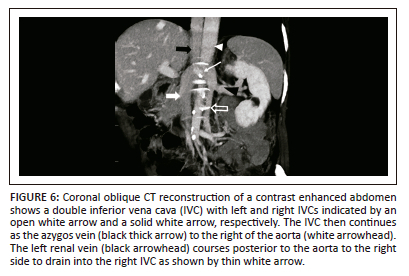

Double inferior vena cava with a retroaortic left renal vein and azygos continuation of the inferior vena cava

This congenital variation occurs when the supracardinal vein and the dorsal limb of the renal collar persist while the ventral limb regresses and the subcardinal-hepatic anastomosis does not form.1,25 These are extremely rare and detected incidentally. Very few cases of right-sided varicocele have been reported in patients with a double IVC and azygos or hemiazygos continuation.25,26 The imaging findings are similar to azygos continuation of the IVC except there is a double IVC instead of the normal right-sided IVC and the left renal vein has a retroaortic course25 (Figure 6). Clinical implications of this variation are to avoid misdiagnosis as lymphadenopathy and preoperative surgical planning.25